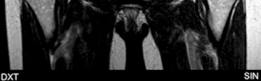

Advanced imaging with computed tomography (CT) with 3D reconstruction is increasingly utilized. 3D CT allows for precise mapping of the bony anatomy, evaluation of acetabular version, and virtual surgical planning. Magnetic resonance imaging (MRI) or MR arthrography is routinely obtained to evaluate the integrity of the labrum, articular cartilage, and ligamentum teres. Concomitant intra-articular pathology is highly prevalent in dysplastic hips and must be factored into the surgical plan, often necessitating a combined approach with hip arthroscopy or open arthrotomy.